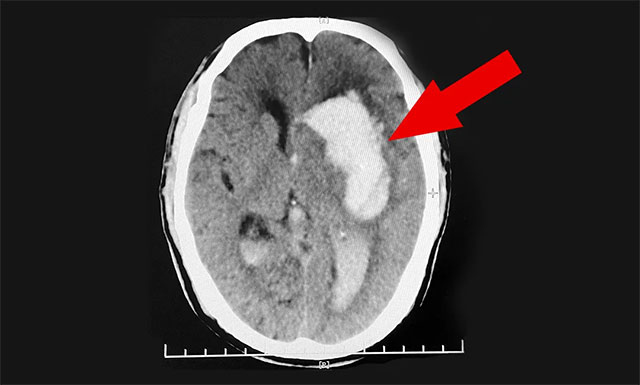

送到医院后,紧急行头部CT检查,根据影像提示及其他相关检查,患者程先生左侧基底节区脑出血,并破入脑室,且出血量很大,临近功能区;伴左侧高颅压,其双侧大脑半球深部多发腔梗,情况非常危急。医生把情况告知郭女士,若手术治疗风险很大,即使保住了生命,也很可能长期偏瘫在床,让她及家属做好心理准备。郭女士听后感到“天塌了一般”,简直无法接受。

▲ 患者突发脑出血昏迷不醒,病情危急需及时手术

鉴于患者病情危重,潘仁龙主任紧急组织专家团队会诊,根据患者目前的病情、病症及影像检查结果,潘主任与吴博士一致认为患者程先生脑出血严重,已破入脑室,出血量又大,且左侧高颅压,其血压收缩压当时更是高达208mmHg,如果不及时手术治疗,还会有再次出血的风险,因此患者需及早手术清除颅内血肿和降颅压,否则随时会有生命危险。